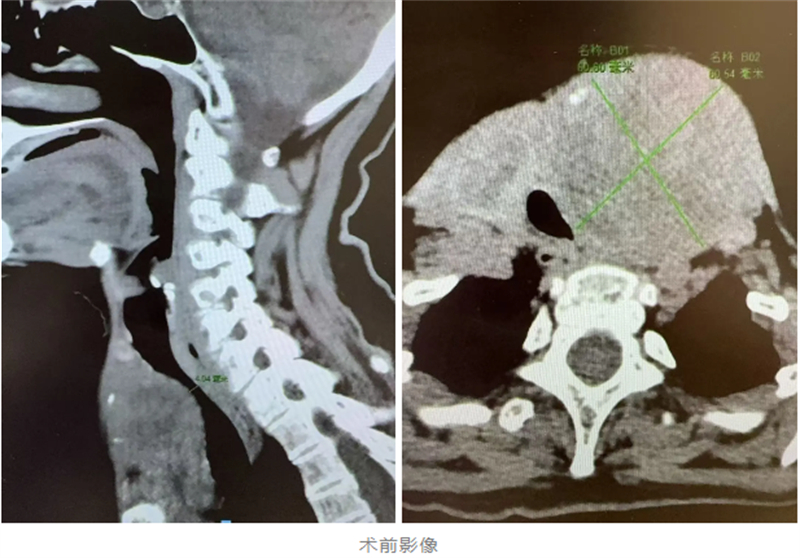

這場手術(shù)是對技術(shù)與意志的雙重考驗(yàn)。麻醉科醫(yī)生在術(shù)前反復(fù)研究患者的頸部CT,多次預(yù)演插管細(xì)節(jié),最終在可視喉鏡的引導(dǎo)下,將導(dǎo)管精準(zhǔn)插入被腫瘤壓迫到僅剩約35%面積的氣管里,為手術(shù)的順利完成奠定了堅(jiān)實(shí)的基礎(chǔ)。

手術(shù)過程中,乳腺甲狀腺外科團(tuán)隊(duì)面臨著前所未有的挑戰(zhàn)。腫瘤牢牢長在左頸內(nèi)靜脈及食管表面,稍有不慎就可能引發(fā)致死性大出血或食管破裂。然而,在呂侶博士的帶領(lǐng)下,團(tuán)隊(duì)利用顯微微創(chuàng)技術(shù),在0.5毫米的安全距離內(nèi)小心翼翼地剝離腫瘤。同時(shí),他們還特別注意保護(hù)左側(cè)喉返神經(jīng)及聲帶功能。